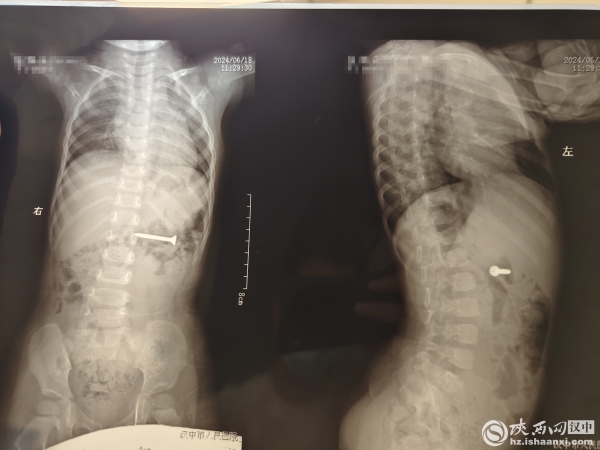

6月18日,汉中市人民医院接诊了一位误吞螺丝钉的幼儿,经过多学科对症治疗,成功取出一颗长约3.4厘米的螺丝钉。

“当天11时左右,幼儿家属带着幼儿到儿科门诊就诊,幼儿年龄一岁八个月,家属称小孩疑似吞下了一颗螺丝钉,然后出现发热……”汉中市人民医院儿科医师任烽荣介绍说,在得知情况后,对幼儿做了胸腹片检查,通过检查发现,幼儿消化道内存在一钉状异物。

在经过20分钟的手术后,钉状异物被成功取出。经测量,异物为一颗长约3.4厘米的螺丝钉。     小孩好奇心较重,喜欢用嘴来探索世界,因此儿童误吸、误吞异物的案例时有发生。汉中市人民医院儿科副主任医师赵有丽提醒广大家长,要给宝宝养成良好的习惯,让宝宝知道什么东西能吃,什么东西不能吃,在购买玩具时要查看一下玩具是否能够拆卸,容易拆卸和脱落的零件也有可能会导致孩子误吞。同时像小剪刀、纽扣、纽扣电池、硬币等高危物品要妥善存放,不要摆在孩子能接触到的范围内。如果宝宝误吞下异物,在此期间切勿给宝宝喂水喂食,并尽快前往医院就诊。